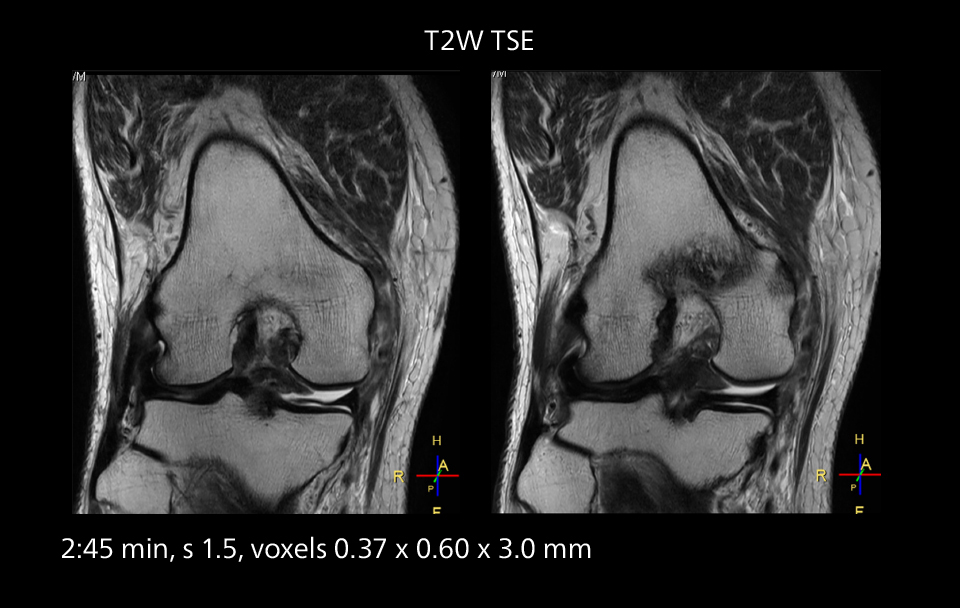

Images showing a posterior cruciate ligament (PCL) tear, a detached medial collateral ligament (MCL) on the tibial side and an intact anterior cruciate ligament (ACL). SmartPath to Elition X helped reduce scan time compared to previous imaging while maintaining resolution.

Crisp images are obtained with high resolution and short scan times using Elition X. A cyst can be seen.